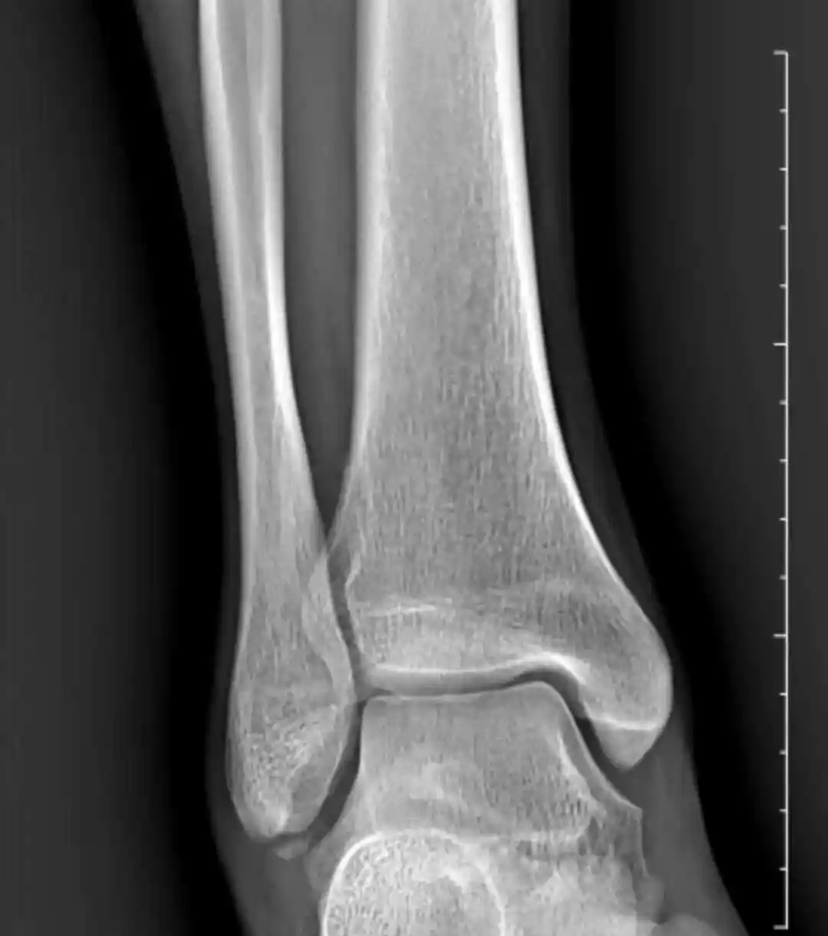

1,急性踝关节扭伤是否需要X线检查?

答:需要!扭伤主要排除骨性结构异常:骨折/脱位。 一旦出现骨折/脱位的处理原则和治疗方案不一样! 【一般踝关节X片报告提示踝关节(软组织)肿胀】说明骨头没事,韧带损伤!

踝关节周围小撕脱骨折相当于韧带从骨头表面撕脱下来,等同于韧带损伤,不是骨折!(治疗原则同踝关节急性韧带损伤)